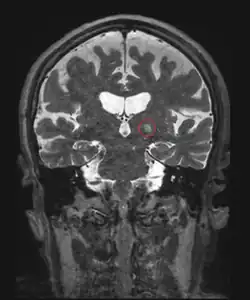

El origen del HIFU no es reciente, se remonta a los años 1950 en los EE. UU., donde empezaron las primeras investigaciones por parte de Lindstrom y los hermanos Fry en cerebros de animales. Fue posteriormente cuando algunos discípulos chinos, de los investigadores americanos se situaron al frente de las investigaciones de esta tecnología hasta llegar, a principios de los años 1990, al uso clínico en pacientes reales. El MRgFUS guía el haz de ultrasonidos mediante imagen térmica en tiempo real guiada por Resonancia Magnética, gracias a este nueva técnica es posible conseguir una alta precisión en la sonicación así como control de la temperatura de ablación.